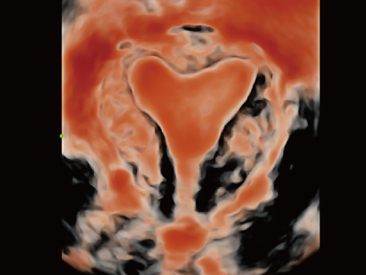

Resona 7

?? Resona 7? ???? ??? ?? ???? ??? ??? ???? ??? ?? ???? V Flow? ?? CNS ??? ?? 3D ??? ???? ?? ???? ?? ??? ?? ?? ?? ??? ??????. ???? ??? ??? ?? ?? ??? ??? ?? ?? ??? ??? Resona 7? ??? ???? ???? ??? ??? ??? ????.